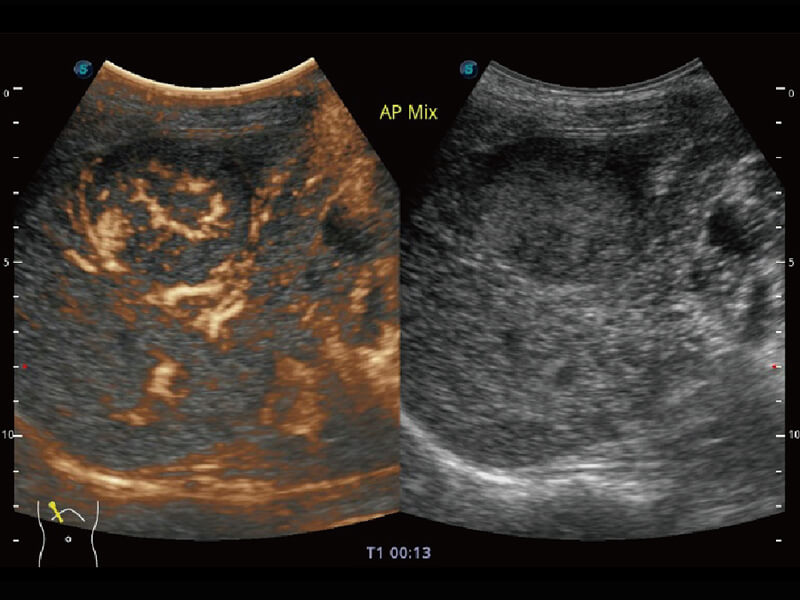

Micro F 显微血流成像 明察秋毫